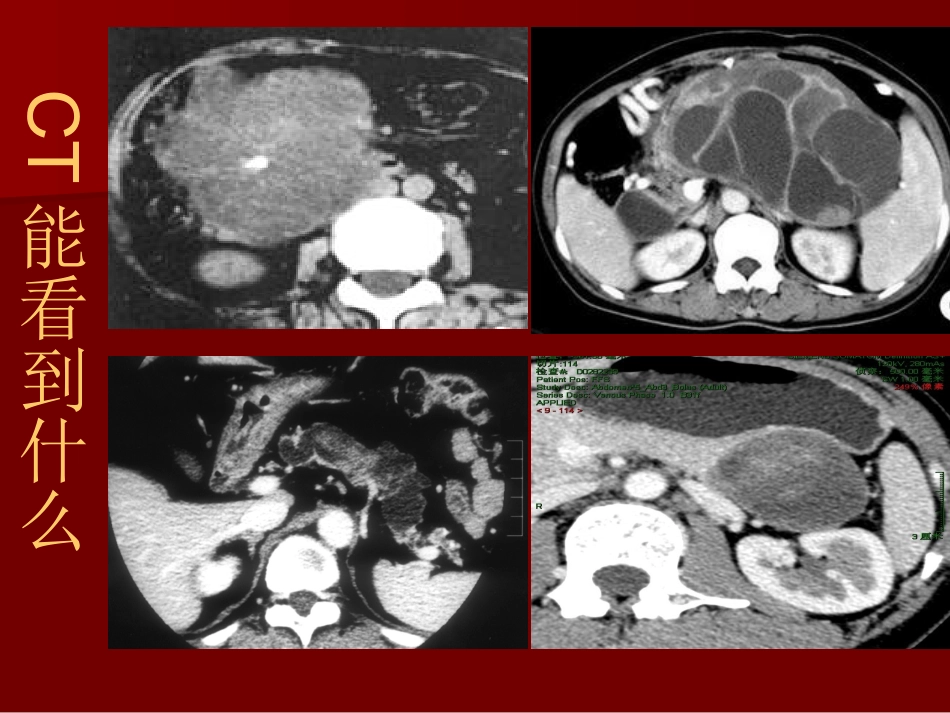

胰腺囊性肿瘤的胰腺囊性肿瘤的CTCT诊诊断断池州市人民医院医学影像科钱池州市人民医院医学影像科钱彬彬CT能看到什么临床上常见的胰腺囊性肿瘤主要包括临床上常见的胰腺囊性肿瘤主要包括浆液性囊性肿瘤(浆液性囊性肿瘤(SCNSCN))实性假乳头状瘤(SPN)黏液性囊性肿瘤(MCN)导管内乳头状黏液瘤(IPMT)非黏液性,良性或低度恶性黏液性,有潜在或明显恶性倾向一、浆液性囊腺瘤一、浆液性囊腺瘤(SCN)(SCN)1/31/3患者无临床症状,偶然发现患者无临床症状,偶然发现可发生于胰腺任何部位,可发生于胰腺任何部位,中老年女性多见中老年女性多见起源于胰腺腺泡细胞和管状细胞起源于胰腺腺泡细胞和管状细胞病理分型:病理分型:微囊型微囊型:(:(microcysticadenomasmicrocysticadenomas)常见)常见80-90%80-90%巨囊型巨囊型::(oligocysticadenomas)(oligocysticadenomas)少见少见10-2010-20%%微囊型影像学最具有特征性微囊型影像学最具有特征性(一)微囊型囊腺瘤(一)微囊型囊腺瘤肿瘤大小不一,边缘光整肿瘤大小不一,边缘光整切面海绵状或蜂窝状,由无数小囊组成(切面海绵状或蜂窝状,由无数小囊组成(1mm-2c1mm-2cmm),薄壁),薄壁中央不规则星状瘢痕,日光放射状钙化中央不规则星状瘢痕,日光放射状钙化囊内充满透明的水样液体囊内充满透明的水样液体微囊型囊腺瘤的微囊型囊腺瘤的CTCT表现表现分叶状肿块,边缘清晰,分叶状肿块,边缘清晰,囊腔较小,多<囊腔较小,多<2cm2cm,呈蜂窝状改变,,呈蜂窝状改变,薄壁,壁和分隔强化,薄壁,壁和分隔强化,不侵犯邻近结构不侵犯邻近结构钙化钙化特征性改变:中央星状瘢痕,日光放射状特征性改变:中央星状瘢痕,日光放射状钙化钙化微囊型浆液性囊腺瘤微囊型浆液性囊腺瘤中心钙化蜂窝状改变微囊型浆液性囊腺瘤微囊型浆液性囊腺瘤CT平扫增强微囊型浆液性囊腺瘤微囊型浆液性囊腺瘤中央日光放射状钙化蜂窝状改变微囊型浆液性囊腺瘤CT平扫CT增强MRI增强平扫增强微囊型浆液性囊腺瘤(二)巨囊型浆液性囊腺瘤(二)巨囊型浆液性囊腺瘤较微囊性少见,多位于胰头较微囊性少见,多位于胰头容易误诊为假囊肿或粘液性囊腺瘤容易误诊为假囊肿或粘液性囊腺瘤生物学行为与微囊型相似,影像表现不同生物学行为与微囊型相似,影像表现不同CTCT表现表现单囊或多囊,子囊直径均大于单囊或多囊,子囊直径均大于2c2cmm一般一般2-6cm2-6cm分叶状或类圆形分叶状或类圆形壁薄,可见分隔,边缘清晰壁薄,可见分隔,边缘清晰囊壁轻度强化或无强化囊壁轻度强化或无强化无乳头状突起无乳头状突起钙化少见钙化少见二、胰腺粘液性囊腺肿瘤二、胰腺粘液性囊腺肿瘤多见于中老年女性,好发于胰腺体尾部多见于中老年女性,好发于胰腺体尾部临床症状:腹痛、腹部包块、黄疸临床症状:腹痛、腹部包块、黄疸多无慢性胰腺炎及糖尿病史多无慢性胰腺炎及糖尿病史潜在恶性或恶性病变潜在恶性或恶性病变病理分型:腺瘤病理分型:腺瘤交界性交界性腺癌腺癌胰腺粘液性囊腺肿瘤胰腺粘液性囊腺肿瘤CTCT表现表现大单囊或几个大囊组成,大单囊或几个大囊组成,囊壁厚薄不均匀伴有强化,囊壁厚薄不均匀伴有强化,囊壁和分隔钙化(边缘钙化),囊壁和分隔钙化(边缘钙化),不规则厚壁伴壁结节,提示恶性不规则厚壁伴壁结节,提示恶性胰管扩张少见,胰管扩张少见,可伴有胰腺炎可伴有胰腺炎粘液性囊腺瘤粘液性囊腺癌壁结节不规则厚壁交界性粘液性囊腺肿瘤交界性粘液性囊腺肿瘤粘液性囊腺瘤粘液性囊腺瘤粘液性囊腺癌粘液性囊腺癌粘液性囊腺瘤粘液性囊腺瘤粘液性囊腺癌壁和分隔钙化明显厚壁粘液性囊腺癌粘液性囊腺癌三、胰腺导管内乳头状粘液性肿瘤三、胰腺导管内乳头状粘液性肿瘤(IPMT)(IPMT)好发于中老年男性好发于中老年男性常见症状:腹痛、黄疸、脂肪泻,消瘦、易常见症状:腹痛、黄疸、脂肪泻,消瘦、易被误诊为慢性胰腺炎被误诊为慢性胰腺炎胰管内大量粘液潴留胰管内大量粘液潴留十二指肠乳头开口由于粘液流过而扩大十二指肠乳头开口由于粘液流过而扩大很少有浸润倾向很少有浸...